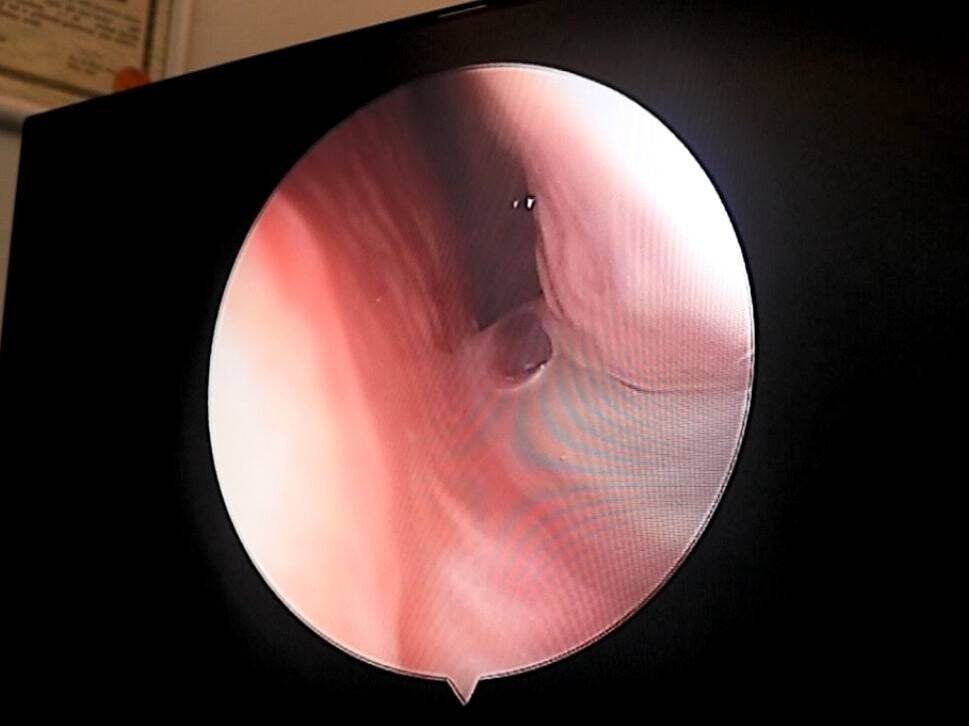

Türkiye genelinde ve Samsun'da son aylarda acil servis ve polikliniklerde solunum yolu hastalıklarına bağlı şikayetler oldukça arttı. Vatandaşlar kamu ve özel hastanelerde tedavi ve tanı alabilmek için eskiye nazaran uzun kuyruklar oluşturdu. Konu hakkında açıklamalarda bulunan Medicana Intarnational Samsun Hastanesi KBB Hastalıkları Kliniği'nden Opr. Dr. Yusuf Şentürk, önemli uyarılarda bulundu.

Eskiye nazaran daha uzun süren solunum yolu rahatsızlıklarının nedenini açıklayan Opr. Dr. Yusuf Şentürk, "Bu sene 3'lü bir salgınla karşı karşıyayız. Çok bilinmese de Covid-19 yine pik düzeyinde. Bunun yanında grip ve beta enfeksiyonu da yoğun bir şekilde görülüyor. Bu da 3'lü bir salgına neden olmuştur. Kişiler virüslerin hepsini aynı anda kapamaz ama tekrar kapalı ortama geçiş yaptık. Kış mevsimi nedeniyle vaka sayıları arttı. Bu sene beta ve grip salgını da artınca 3'ü bir arada görüldüğü için hastalıklar sanki "geçmiyor" gibi düşünülmeye başlandı. Hastalar özellikle çocuklar Beta enfeksiyonuna yakalanıyor. Bağışıklık sistemi düşüyor. Peşinde gribe yakalanıyor belki arada Covid-19 da geçiriyor. O nedenle de kapalı ortamda bu yıl da maske uygulamasının devam etmesi gerekirdi. Doğada milyonlarca virüs var. Saydığımız virüslerin haricinde nezle virüsleri de var. Bunlar insanlarda tekrarlayan enfeksiyonlara neden oluyor. Kişiler nezle virüsüne yakalandığı zaman başka virüslere de yakalanabiliyor. Gribin de kendi içinde çeşitleri var. Bunlar ardışık şekilde enfeksiyonlara neden olabiliyor. İnsanlar maske takmadığı için ardışık enfeksiyonlar meydana gelmekte ve sanki hiç iyileşmiyorlarmış gibi bir intiba oluşuyor" dedi.